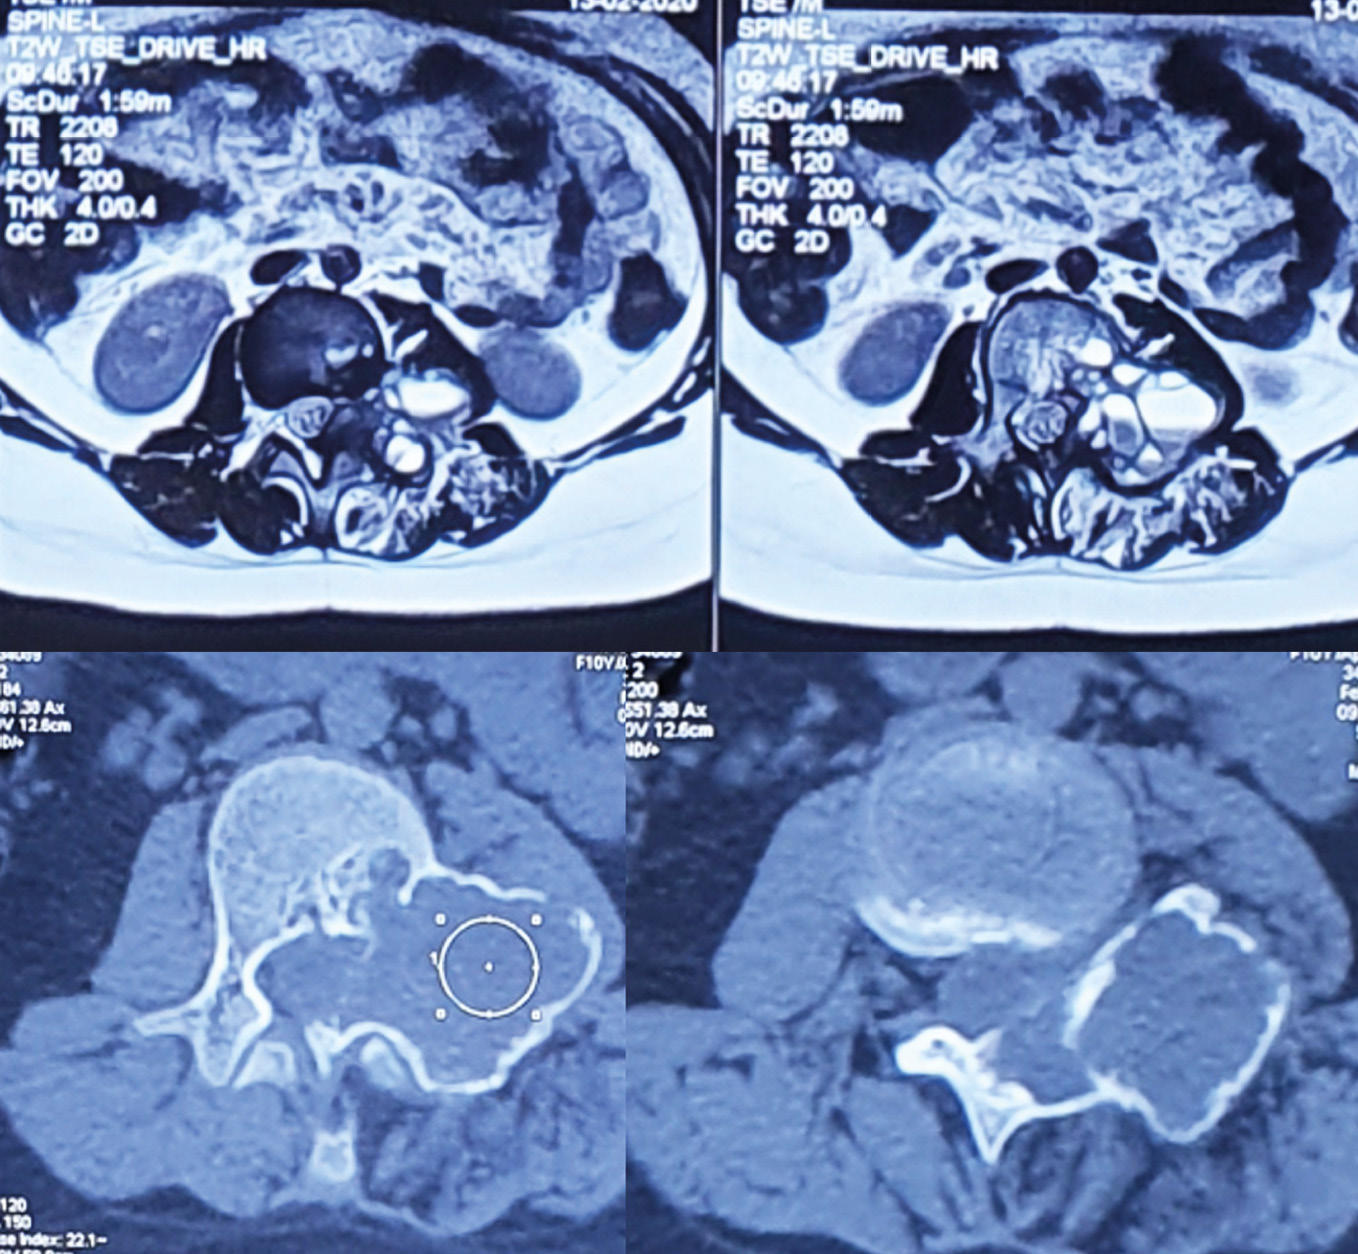

Пункция аневризмальной кисты проводилось у 48 пациентов (62 %) в качестве лечебно-диагностической цели, в 30 случаях (38 %) проведено открытое хирургическое лечение без предварительной пункции (рис. 1). В 16 (33 %) случаях при наблюдении отмечены признаки репарации патологического очага. В 35 (73 %) — отмечено снижение активности кисты, в виде уменьшения размеров, снижения степени стеноза позвоночного канала, снижения внутрикистного давления в мм. водного столба. При проведении пункции важным являлась оценка внутрикистного даления. Оценку проводили путём измерения давления водного столба. В среднем от 172 до 330 мм водного столба. Большинство выполненных пункций (37 пациента) показало высокое внутрикистное давление. В 9 случаях давление было незначительным.

Рис. 1. Пункция аневризмальной кисты С4-5 с измерением давления по шкале в мм.водного столба

Fig. 1. Puncture of aneurysmal cyst C4-5 with measurement of pressure in mm water column

Пункционное лечение аневризмальных кист позволяло снизить риск тяжёлого кровотечения, снизить внутрикистное давление, простимулировать репарацию костной ткани, что снижает интраоперационные риски при открытых операциях, снижает вероятность рецидива, и улучшает послеоперационные результаты. При этом пункцию проводили по возможности не реже чем один раз в 2–3 месяца. Количество пункций составляло от 2 до 6 в зависимости от объёмов патологического очага. Положительная динамик при лечении данной группы пациентов отмечалась не ранее чем через 6 месяцев с момента начала лечения (рис. 2). Критерием положительного результата являлось остановка роста кисты, снижение её активности по сравнению с предыдущими пункциями, формирование зон оссификаци по данным КТ. Оптимальным признаком снижения активности являлось отсутствие активного кровотечения при проведении пункции трепаном.